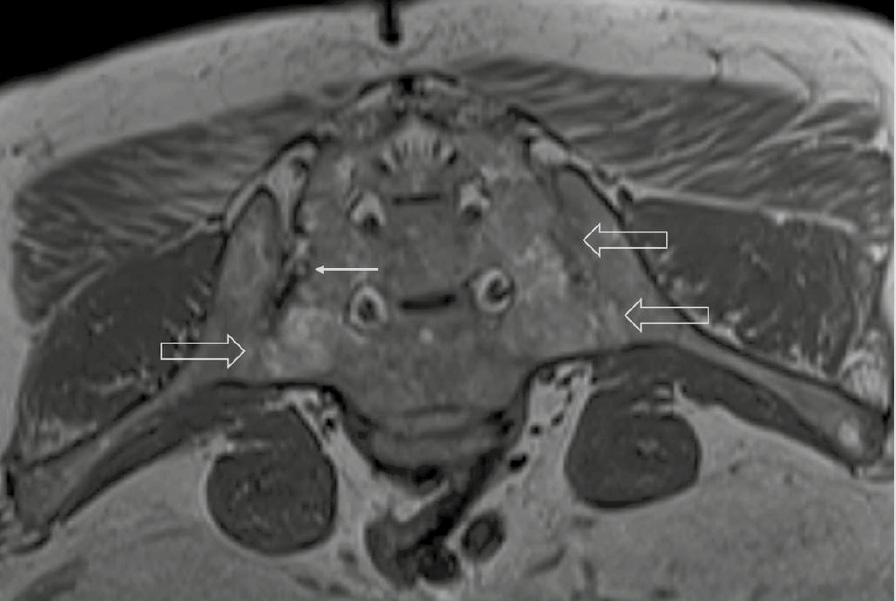

При компьютерной томографии органов грудной клетки данных за «свежие» очаговые и инфильтративные изменения не получено. Увеличения лимфатических узлов подмышечных областей, средостения, корней легких не выявлено. Отмечался усиленный грудной кифоз, обызвествление передней продольной связки, на всем уровне исследования определялись передне-боковые спондилофиты, а также анкилоз большинства реберно-поперечных суставов. По данным рентгенографии кистей (рис. 1, 2) и стоп (рис. 3, 4) диагностированы признаки эрозивного артрита, анкилоз суставов запястья. По данным МРТ крестцово-подвздошных суставов (КПС) определялся неравномерный анкилоз КПС, хрящи по суставным поверхностям неравномерной толщины, примерно на половине протяжении сустава отсутствуют, «суставной промежуток» облитерирован. Неравномерность и нечеткость контура суставных поверхностей за счет множества краевых эрозий справа, единичных – слева, с наличием остеокластоза, в нижнем отделе слева по смежным отделам определяются участки трабекулярного отека, данная находка клинически интерпретирована как двусторонний активный сакроилиит (рис. 5, 6).

Рис. 5. Магнитно-резонансная томография (Т2-взвешенное изображение в поперечной проекции). Протяженные участки анкилоза крестцово-подвздошных сочленений (толстые стрелки), эрозии суставных поверхностей (тонкие стрелки)